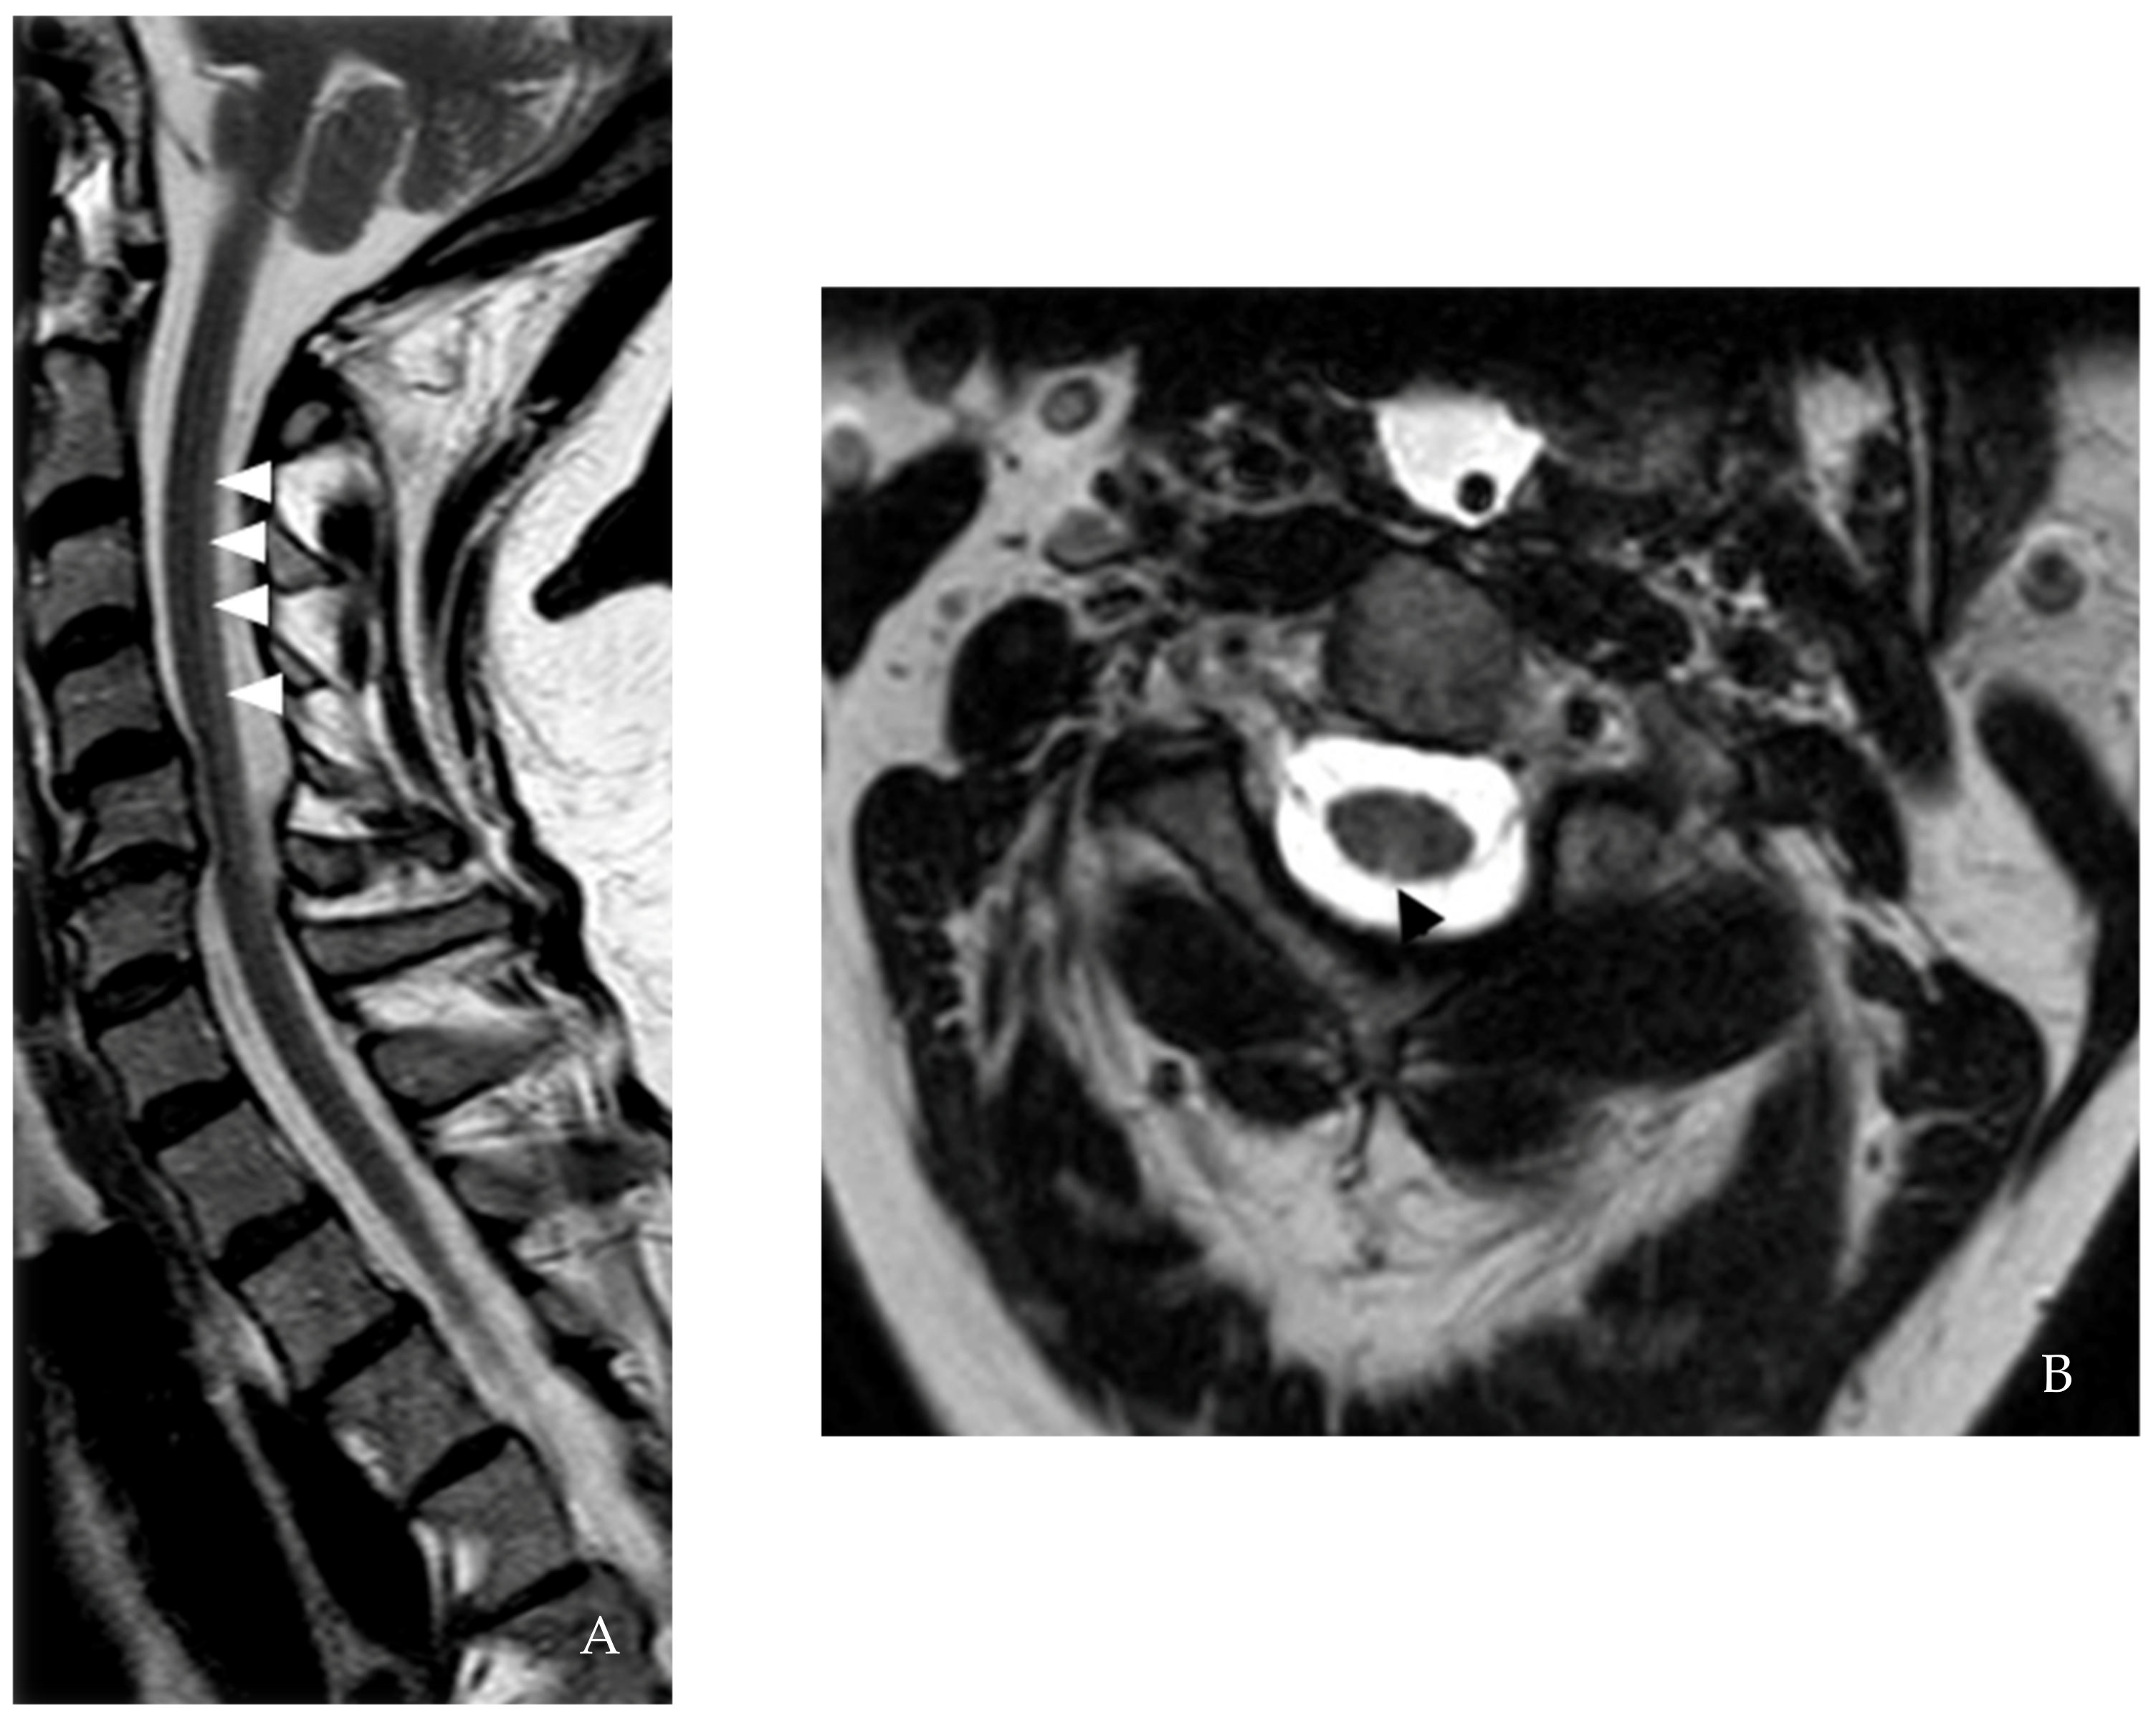

| Brain MRI | 1st event: Nonspecific multifocal T2/ FLAIR WML 2nd event: Nonspecific multifocal T2/ FLAIR WML | Periventricular and juxtacortical lesion, dorsal medullary lesion extending to cervicomedullary junction | Multifocal T2/ FLAIR WML | 1st MRI: Subcortical, periventricular, anterior temporal lobe, medullary lesions 2nd MRI: Stable | Periventricular, anterior cervico- medullary junction lesion | Periventricular and R frontal deep white matter lesions |

| Spinal cord MRI | 1st event: Cervical spine degenerative joint Disease 2nd event: C2-5 dorsal column T2 hyperintensity | C2-3 and T4 T2/ FLAIR lesions | ND | 1st MRI: C3, C5-6, C7-T1, and T8-9 lesions 2nd MRI: New C3 Gd-enhancing lesion | C2, C4-C7 lesion and cervical nerve root enhancement in the central cervical canal | 1st MRI: Age-related L4-5 changes 2nd MRI: C1 contrast-enhancing lesion 3rd MRI: C2 and C5 lesions |